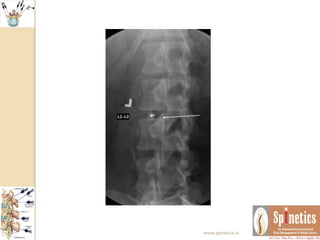

AP and

lateral

fluoroscopic

images

demonstrati

ng needle

position

within the

central third

of the L4–L5

disc prior to

contrast

injection.

AP and lateral fluoroscopic images demonstrati ng needle position withinthe central third of the L4–L5 disc prior to contrast injection. www.spinetics.in